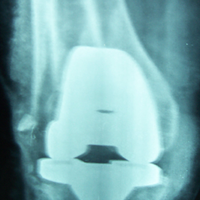

Case:14 Periprosthetic Fracture

60 years old patient with total knee replacement on left knee presented with open grade 1 injury. Debridement & slab given on emergency bases. Fixation with plate & screws done. Union was seen after 6 months.

Pre-Op AP

Pre-Op Lat.

Immdiate Post-op

1 and half months Post-op

2 and half months Post-op

3 and half months Post-op

4 and half months Lateral

6 Years Follow-Up